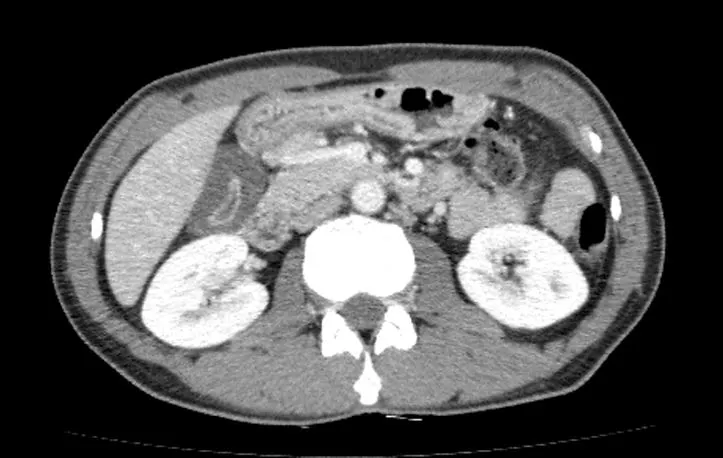

이런 경우는 간에 문제가 있거나 담도(간에서 만들어지는 담즙을 십이지장으로 보내는 관) 에 문제가 있는 경우가 대부분이라서, 정확한 원인 파악을 위해 복부 CT 또는 복부 초음파 등의 검사가 필요하다. 초음파로는 담도의 이상을 확인하지 못하는 경우가 종종 있어서, 복부 CT 검사를 시행하자고 하였다.

간염으로 인해 담낭벽이 두꺼워져 있다.

복부 CT 검사 결과는 암이나 담도염의 소견은 없었고, 담낭벽이 두꺼워져 있으나 담낭이 수축되어 있어 담낭염보다는 간염의 소견으로 생각되었고, 황달수치가 더 올라가면 간이식을 하는 경우도 드물게 있어 환자분에게 설명 후 입원하여 치료하기로 하였다.